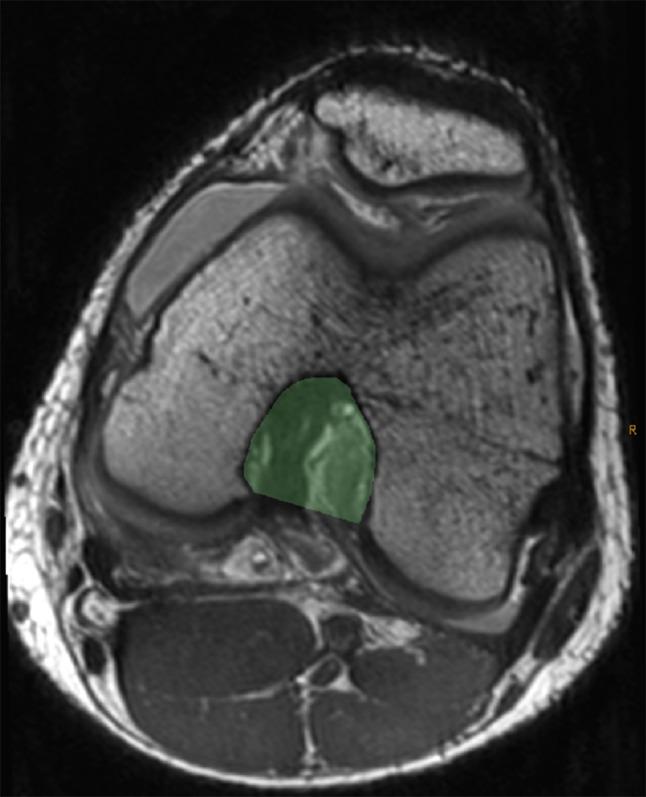

A retrospective review of pediatric patients undergoing knee magnetic resonance imaging (MRI) was performed over a 4-year period. Inclusionary criteria included mid-substance ACL disruption, skeletal immaturity, noncontact injury, without associated ligamentous disruption, and no medical condition associated with ligamentous laxity. MRI studies were analyzed by a pediatric musculoskeletal radiologist, measuring identified bony parameters, and compared with an age-matched control group without ligamentous injury. Data were analyzed using unpaired t-tests and logistic regression.

对4年间接受膝关节磁共振成像(MRI)检查的儿科患者进行回顾性研究。纳入标准包括ACL实质中部断裂、骨骼未成熟、非接触性损伤、无相关韧带断裂,且无与韧带松弛相关的疾病。MRI研究由儿科肌肉骨骼放射科医生进行分析,测量已识别的骨骼参数,并与无韧带损伤的年龄匹配对照组进行比较。数据采用非配对t检验和逻辑回归分析。